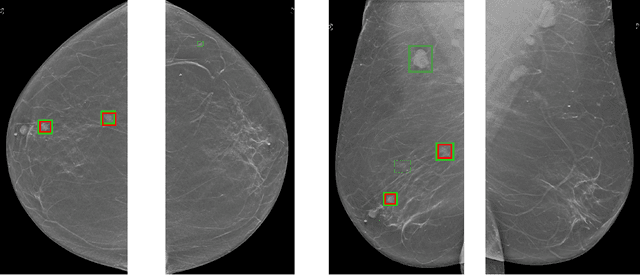

Abstract:Transformer-based detectors have shown success in computer vision tasks with natural images. These models, exemplified by the Deformable DETR, are optimized through complex engineering strategies tailored to the typical characteristics of natural scenes. However, medical imaging data presents unique challenges such as extremely large image sizes, fewer and smaller regions of interest, and object classes which can be differentiated only through subtle differences. This study evaluates the applicability of these transformer-based design choices when applied to a screening mammography dataset that represents these distinct medical imaging data characteristics. Our analysis reveals that common design choices from the natural image domain, such as complex encoder architectures, multi-scale feature fusion, query initialization, and iterative bounding box refinement, do not improve and sometimes even impair object detection performance in medical imaging. In contrast, simpler and shallower architectures often achieve equal or superior results. This finding suggests that the adaptation of transformer models for medical imaging data requires a reevaluation of standard practices, potentially leading to more efficient and specialized frameworks for medical diagnosis.

Abstract:3D imaging enables a more accurate diagnosis by providing spatial information about organ anatomy. However, using 3D images to train AI models is computationally challenging because they consist of tens or hundreds of times more pixels than their 2D counterparts. To train with high-resolution 3D images, convolutional neural networks typically resort to downsampling them or projecting them to two dimensions. In this work, we propose an effective alternative, a novel neural network architecture that enables computationally efficient classification of 3D medical images in their full resolution. Compared to off-the-shelf convolutional neural networks, 3D-GMIC uses 77.98%-90.05% less GPU memory and 91.23%-96.02% less computation. While our network is trained only with image-level labels, without segmentation labels, it explains its classification predictions by providing pixel-level saliency maps. On a dataset collected at NYU Langone Health, including 85,526 patients with full-field 2D mammography (FFDM), synthetic 2D mammography, and 3D mammography (DBT), our model, the 3D Globally-Aware Multiple Instance Classifier (3D-GMIC), achieves a breast-wise AUC of 0.831 (95% CI: 0.769-0.887) in classifying breasts with malignant findings using DBT images. As DBT and 2D mammography capture different information, averaging predictions on 2D and 3D mammography together leads to a diverse ensemble with an improved breast-wise AUC of 0.841 (95% CI: 0.768-0.895). Our model generalizes well to an external dataset from Duke University Hospital, achieving an image-wise AUC of 0.848 (95% CI: 0.798-0.896) in classifying DBT images with malignant findings.